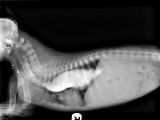

Le mégaœsophage est une atteinte de l'œsophage du chien, congénitale ou acquise, qui se trouve être distendu et dans l'impossibilité de pousser les aliments vers l'estomac et de les y retenir. L'animal peut difficilement avaler et, pour s'assurer que le bol alimentaire fasse son chemin normalement, on fait manger le chien aussi verticalement que possible, d'où cette chaise spéciale.